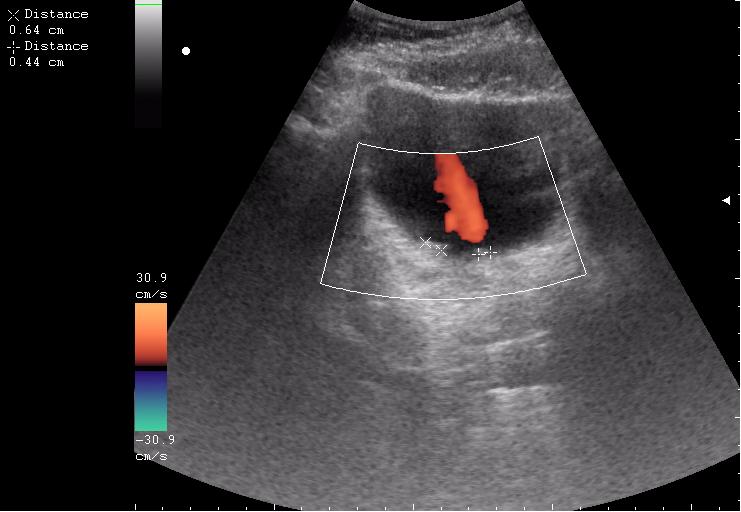

Продольное сканирование мочевого пузыря После легкой перкуссии мочевого пузыря